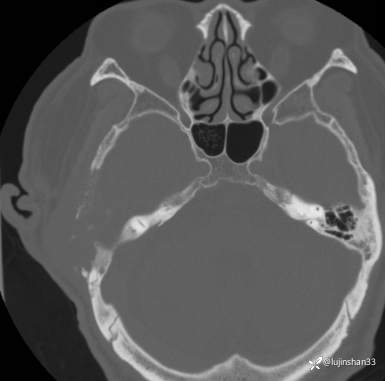

CT:

简要病史:患者2022年10月掏耳后出现右耳疼痛,流水,伴血性分泌物,伴听力下降,无头痛头晕,无口角歪斜,自行购买滴耳液及口服罗红霉素,效果不佳。后右耳痛加剧,偶需止疼药治疗。后于XXXXXX医院行中耳乳突CT检查示“右耳恶性肿瘤?坏死性外耳道炎?”颅脑磁共振平扫示“脑内多发缺血灶、梗塞灶,脑白质疏松,脑萎缩、右中耳恶性占位。”建议上级医院治疗。2023-4-13就诊于我科门诊,行右外耳道病理活检示“鳞状上皮黏膜慢性炎伴急性炎,可见较多炎性坏死,部分上皮增生明显伴不典型增生,小灶上皮呈重度异型增生伴癌变。”建议手术治疗。今患者为求进一步诊治,门诊以“颞骨占位(右)“收治入院。